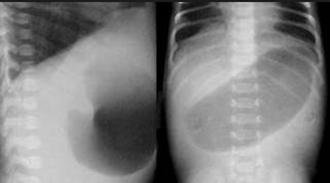

Los recién nacidos con atresia intestinal, suelen ser diagnosticados prenatalmente, en la ecografía obstétrica se suele encontrar polihidramnios, característico de obstrucciones intestinales. Los niños con atresia intestinal suelen nacer a término, no está relacionado con la prematurisas. Asimismo, el ultrasonido obstétrico puede identificar la dilatación intestinal en la zona atrésica. La ausencia de adecuados controles prenatales evita el diagnóstico precoz. Al nacimiento presentan signos de obstrucción intestinal el primer día de vida. El diagnóstico se confirma con radiografía toracoabdominal en posición vertical, las radiografías en decúbito lateral son una opción. En la siguiente tabla se muestran diferencias las formas de presentación de la atresia duodenal y yeyunoileal.

Radiografía Signo de la “doble burbuja”. No pasaje de gas distal. En caso haya pasaje de escaso gas distal, podemos sospechar de una estenosis duodenal

Recuerda

El signo radiológico de “doble burbuja”, no es exclusivo de la atresia duodenal, otras patologías como el páncreas anular y la malrotación intestinal también pueden manifestarse con este signo radiológico.